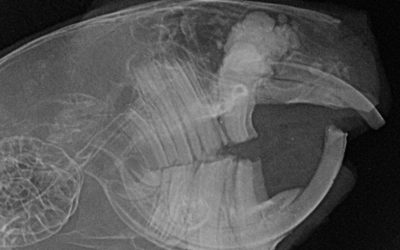

Was in der Datei landet ... ist entweder ein Beweis oder eine unangenehme Überraschung. Aber diese Überraschung ermöglicht uns, ein Problem abzustellen. Schmerz zu beenden. Für diesen Artikel habe ich einige Röntgenaufnahmen von Zähnen ausgewählt. Fast alle Tiere...